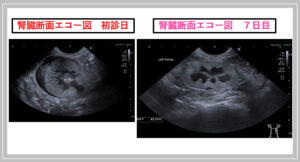

【こんな症例もありますシリーズ832】 『 セカ…

↑ 上の写真は、腎結石から尿管結石が連なっている症例のレントゲン写真です。・◆ 左の大きな白い部分が、腎結石です。・◆ 腎臓の右に続く線状の白い部分は、尿路結石です。  参照サイト:https://00m.in/dsGDy…